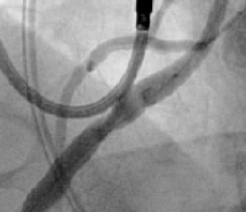

RCA Ostial Stenosis

Prior to stent deployment

Stent protruding into aorta

Post-dilatation with FLASH

TRUE 360° result